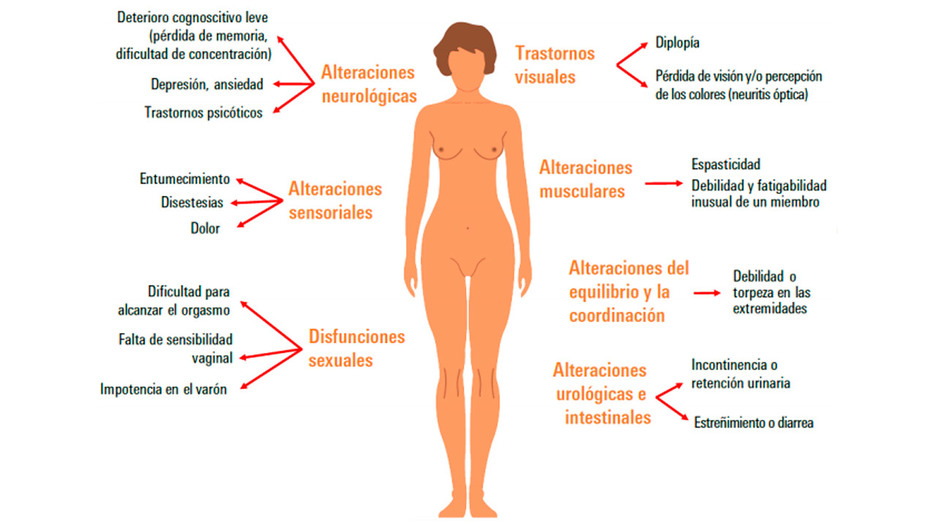

Manifestaciones clínicas de la esclerosis múltiple.

Además, subrayan que la esclerosis se manifiesta mediante variados síntomas como parestesias en extremidades, trastornos visuales, debilidad muscular o fatiga inusual de un miembro, alteraciones leves de la marcha o trastornos emocionales, entre otros. Junto a esto, afirman que el curso de la enfermedad es habitualmente variable y comienza entre los 16 y los 50 años, afectando hasta cuatro mujeres por cada hombre; se estima que reduce la esperanza de vida en hasta 9 años en los hombres y 14 años en las mujeres.